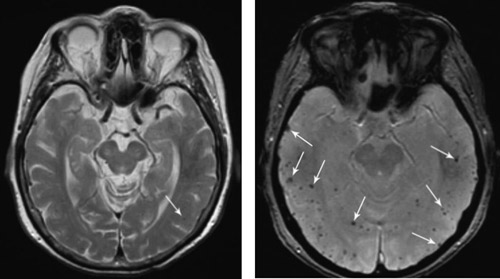

Mikroblødninger kan føre til residiverende episoder med transitoriske nevrologiske utfall. Blødningene etterlater hemosiderinavleiringer kortikalt-subkortikalt. Disse visualiseres ikke på CT og er vanskelig å se på vanlige MR-bilder. Bildet til venstre viser en mulig avleiring på venstre side, markert med pil, som ble tolket som uspesifikk, ellers normale funn. Symptomene mistolkes ofte som transitoriske iskemiske attakker (TIA). Gjentatte mikroblødninger kan fører til langsomt progredierende demens.

På MR med spesielle gradientekkosekvenser trer avleiringene tydelig frem. Gammelt blod fremstår som mørkt (signal void). Mikroblødningene fremstår da som flere punktformige avleiringer i periferien. På bilde til høyre ses flere avleringer, de største er markert med piler.